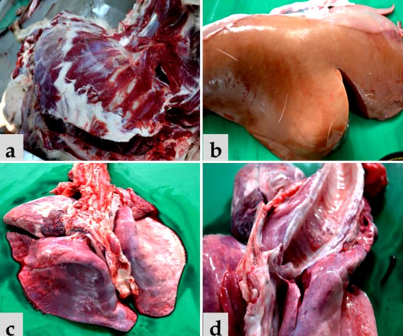

Post-mortem of heavily pregnant ewe found dead. Pregnant with 3 lambs. Diagnosis?

Ketosis/Pregnancy toxaemia/twin lamb disease. Causes hepatic lipidosis.